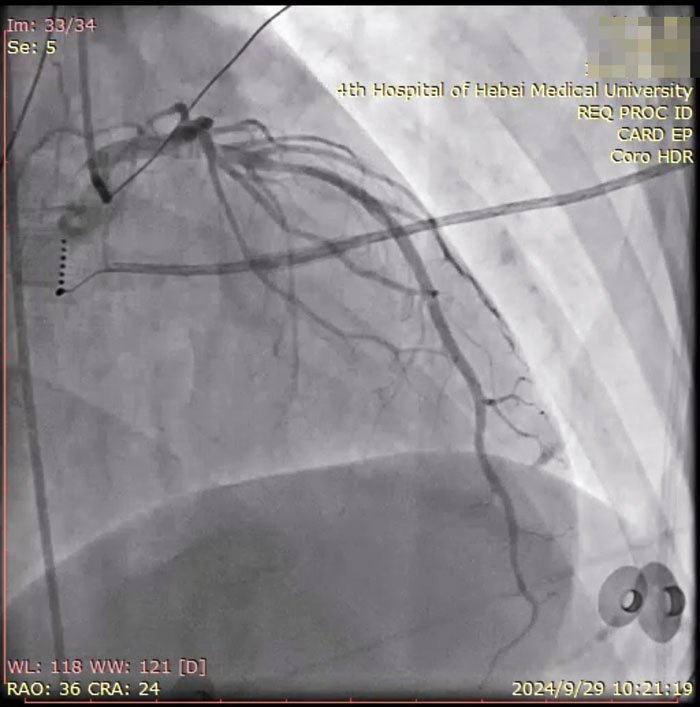

术中患者冠脉造影

手术当日,医护人员连接多导电生理仪和CARTO三维标测系统,对病人进行术前消毒,局麻后穿刺股静脉,操作ST消融导管至右房,建立右心三维解剖。术中,姚铁柱副主任操作ST消融导管经三尖瓣进入右室流出道,于右室流出道后游离壁标测到最早激动靶点,诱发室早形态与原体表心电图室早形态相同,给予放电消融,患者室早消失;继续行冠脉造影术,导管造影结果显示,前降支中段可见约50%局限性狭窄。术毕,患者安返病房,心电图示为“窦律规整”;继续给予心电监测,患者无室早出现,心慌、气短症状消失。根据冠状动脉造影结果对其调节药物治疗,患者胸痛、背痛症状得到缓解。术后仅不到两日,患者便顺利出院。